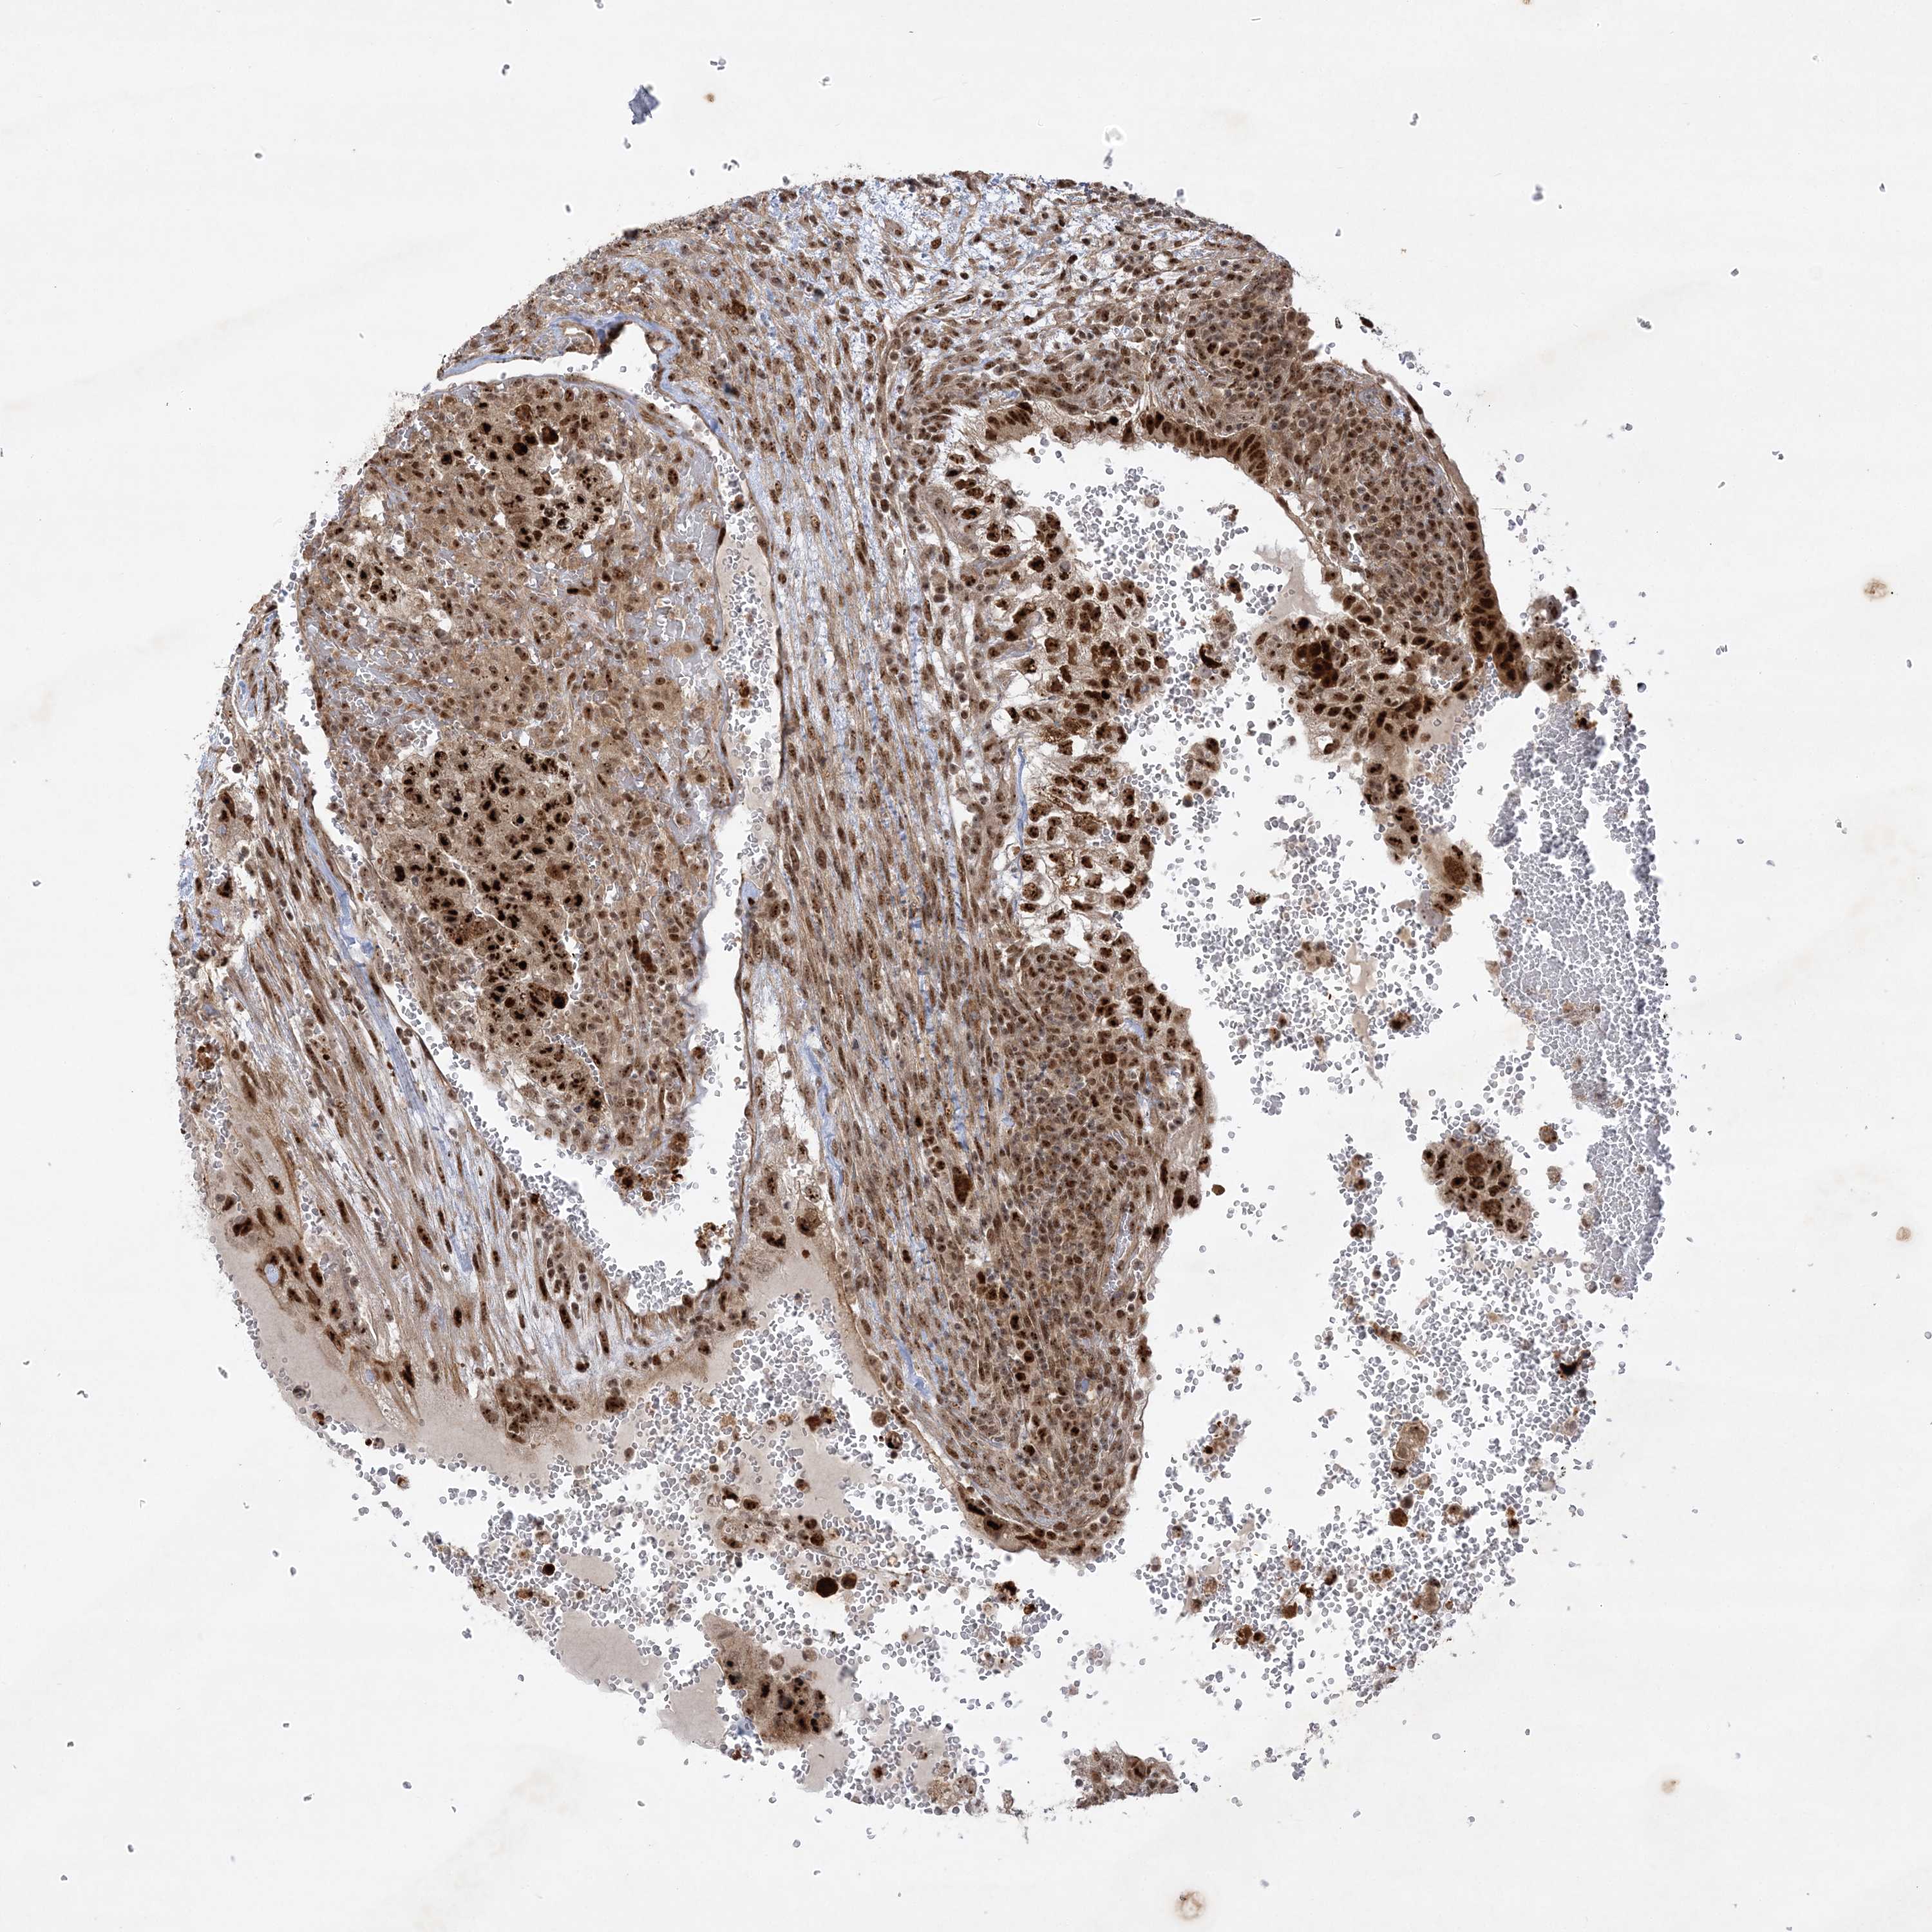

TESTIS CANCER - Protein expressioni

A mouse-over function shows sample information and annotation data. Click on an image to view it in a full screen mode. Samples can be filtered based on level of antibody staining by selecting one or several of the following categories: high, medium, low and not detected. The assay and annotation is described here.

Note that samples used for immunohistochemistry by the Human Protein Atlas do not correspond to samples in the TCGA dataset.

Antibody stainingi

Antibody staining in the annotated cell types in the current human tissue is reported as not detected, low, medium, or high, based on conventional immunohistochemistry profiling in selected tissues. This score is based on the combination of the staining intensity and fraction of stained cells.

Each image is clickable and will lead to virtual microscopy that enables deeper exploration of all samples and also displays staining intensity scores, fraction scores and subcellular localization as well as patient and tissue information for each sample.

Antibody HPA036296

Staining

High

Medium

Low

Not detected

Intensity

Strong

Moderate

Weak

Negative

Quantity

>75%

75%-25%

<25%

None

Location

Nuclear

Cytoplasmic/membranous

Cytoplasmic/membranous,nuclear

Carcinoma, Embryonal, NOS

Seminoma, NOS